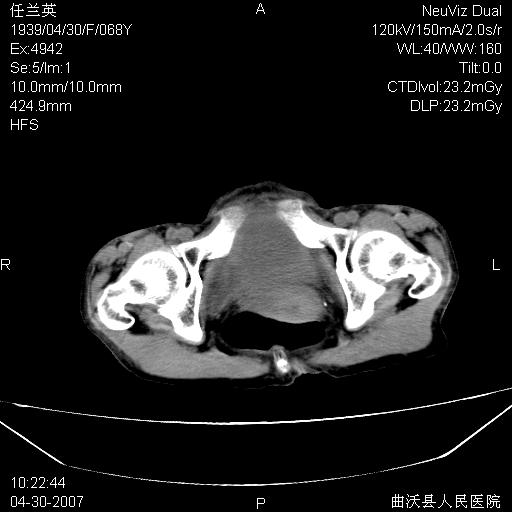

患者,女,68岁,感觉腹部憋涨发硬数天,查b超发现左盆腔有囊性肿物和少量腹水,行ct检查

1.考虑卵巢肿瘤并腹腔广泛性转移可能性大;

支持左侧卵巢恶性肿瘤伴网膜、腹膜广泛转移。

支持:左侧卵巢恶性肿瘤伴网膜、腹膜 腹膜后(淋巴结)广泛转移。

难的一见 典型 - 网膜饼  冰冻骨盆 可以当教学片了